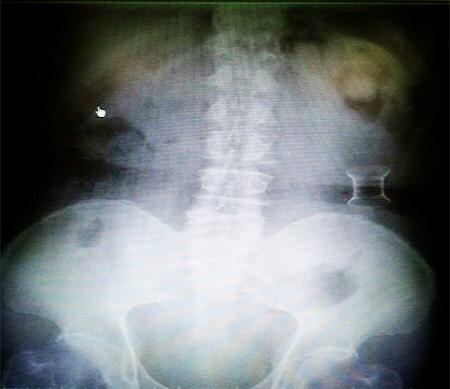

受試患者在結(jié)腸端端吻合術(shù)中,使用我司新研制產(chǎn)品達(dá)到了理想的預(yù)期效果?;颊咝g(shù)后7天、14天X光片顯影,可降解腸道支架均能按研制設(shè)計的預(yù)期時間節(jié)點保持應(yīng)有強度,術(shù)后21天X光片顯示可降解腸道支架已完全破碎,并排出體外。在整個試驗過程中,病患無任何不良反映,耐受良好。